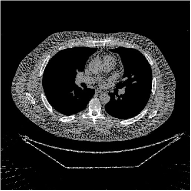

This section compares the reconstruction quality and runtime among the proposed MBIR method, PWLS-ST-, and other three MBIR methods, PWLS-EP, PWLS-DL, and PWLS-ST-. Table I shows that, for both 2D and 3D sparse-view CT reconstructions of the XCAT phantom, the proposed PWLS-ST- model outperforms PWLS-EP and PWLS-ST- in terms of RMSE. In addition, PWLS-ST- using a square transform (of size ) achieves lower RMSE than PWLS-DL using an overcomplete dictionary (of size ) for 2D sparse-view reconstructions. Fig. 3(a) and Fig. 4 show the reconstructed images for 2D and 3D phantom experiments, with different reconstruction models and different number of views. (See the corresponding error maps in the supplement.) The proposed PWLS-ST- consistently gives more accurate image reconstructions compared to other MBIR methods. Specifically, PWLS-ST- has smaller errors in the heart region (see zoom-ins in Fig. 3(a)) of 2D reconstructions than PWLS-DL and PWLS-ST-. In addition, compared to PWLS-ST-, PWLS-DL and PWLS-ST- have some ringing artifacts around the edges with high transition, e.g., edges between air and soft tissues. (See a comparison of profiles of PWLS-ST- and PWLS-ST- in the supplement.) In particular, PWLS-ST- and PWLS-DL give more visible ringing artifacts for 2D reconstruction from fewer views, and PWLS-ST- has these ringing artifacts for 3D reconstructions regardless of the number of views (see zoom-ins in Fig. 4). Table II reports runtimes of different MBIR methods in reconstructing the -views XCAT phantom scan. (FBPConvNet is a non-MBIR method and its runtime for processing a image is approximately one second with a TITAN Xp GPU.) While providing better reconstruction quality, the proposed Algorithm 1 of PWLS-ST- has shorter runtime compared to the algorithms of PWLS-DL and PWLS-ST- in Section III-A. Similar to the PWLS-EP algorithm, the reconstruction time of the PWLS-DL, PWLS-ST-, and PWLS-ST- algorithms can be further reduced by using ordered subsets [51].

Fig. 3(b) shows that when tested on the clinical scan data, the proposed PWLS-ST- method improves reconstruction quality in terms of noise and artifacts removal (e.g., see zoom-ins for soft-issue regions), and edge preservation (e.g., see zoom-ins for bone regions), compared to PWLS-EP and PWLS-ST-. Compared to PWLS-DL, PWLS-ST- achieves comparable image quality, but requires less computational complexity.

The benefit of the proposed PWLS-ST- over PWLS-ST- can be explained when there exist some outliers for some : in (12) gives equal emphasis to all sparse codes – from small to large coefficients that generally correspond to edges in low- and high-contrast regions, respectively – in estimating ; however, PWLS-ST- adjusts to mainly minimize the outliers, i.e., it may not pay enough attention to reconstruct regions with small coefficients. The histogram results in Fig. 1 reveal model mismatch of PWLS-ST- over the iterations. Fig. 3, Fig. 4, and Table I show that PWLS-ST- can moderate model mismatch, and provides more accurate reconstruction than PWLS-ST-.